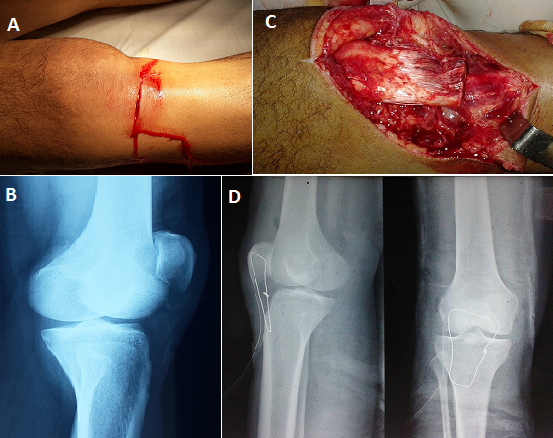

Les plaies du genou avec une section du tendon patellaire et une rupture du rétinaculum patellaire médial sont des lésions rares, et peu rapportés dans la littérature. Le diagnostic est essentiellement clinique et les principaux signes sont l'ascension et la latéralisation de la patella et surtout le déficit de l'extension active du genou. Les sections du tendon patellaire nécessitent une réparation immédiate afin de rétablir l'appareil extenseur et de permettre une récupération fonctionnelle précoce et les ruptures du rétinaculum patellaire médial nécessitent une suture pour éviter l'instabilité patellaire. Nous rapportons un cas rare d'une plaie pénétrante du genou cachant une section complète du tendon patellaire associée à une rupture du rétinaculum patellaire médial. Il s'agit d'un patient âgé de 25 ans, victime d'une agression par coup de couteau entrainant une plaie pénétrante de la face antérieure du genou droit (A). L'examen physique montre un déficit de l'extension active du genou droit. La radiographie standard de face du genou (B) a montré une ascension de la patella. Le patient a bénéficié d'un parage puis exploration chirurgicale de la plaie qui a objectivé une section totale du tendon patellaire et une rupture du rétinaculum patellaire médial (C). La réparation a été réalisée par une suture du rétinaculum médial puis d'une suture tendineuse directe termino-terminale du tendon patellaire par un fil à résorption lente 2mm renforcée par un surjet, suivie d'une suture du péri-tendon et protégée par un cadrage tendineuse au fil d'acier 16/10 (D) enlevée à la 6ème semaine postopératoire avec une bonne évolution à 6 mois de recul.